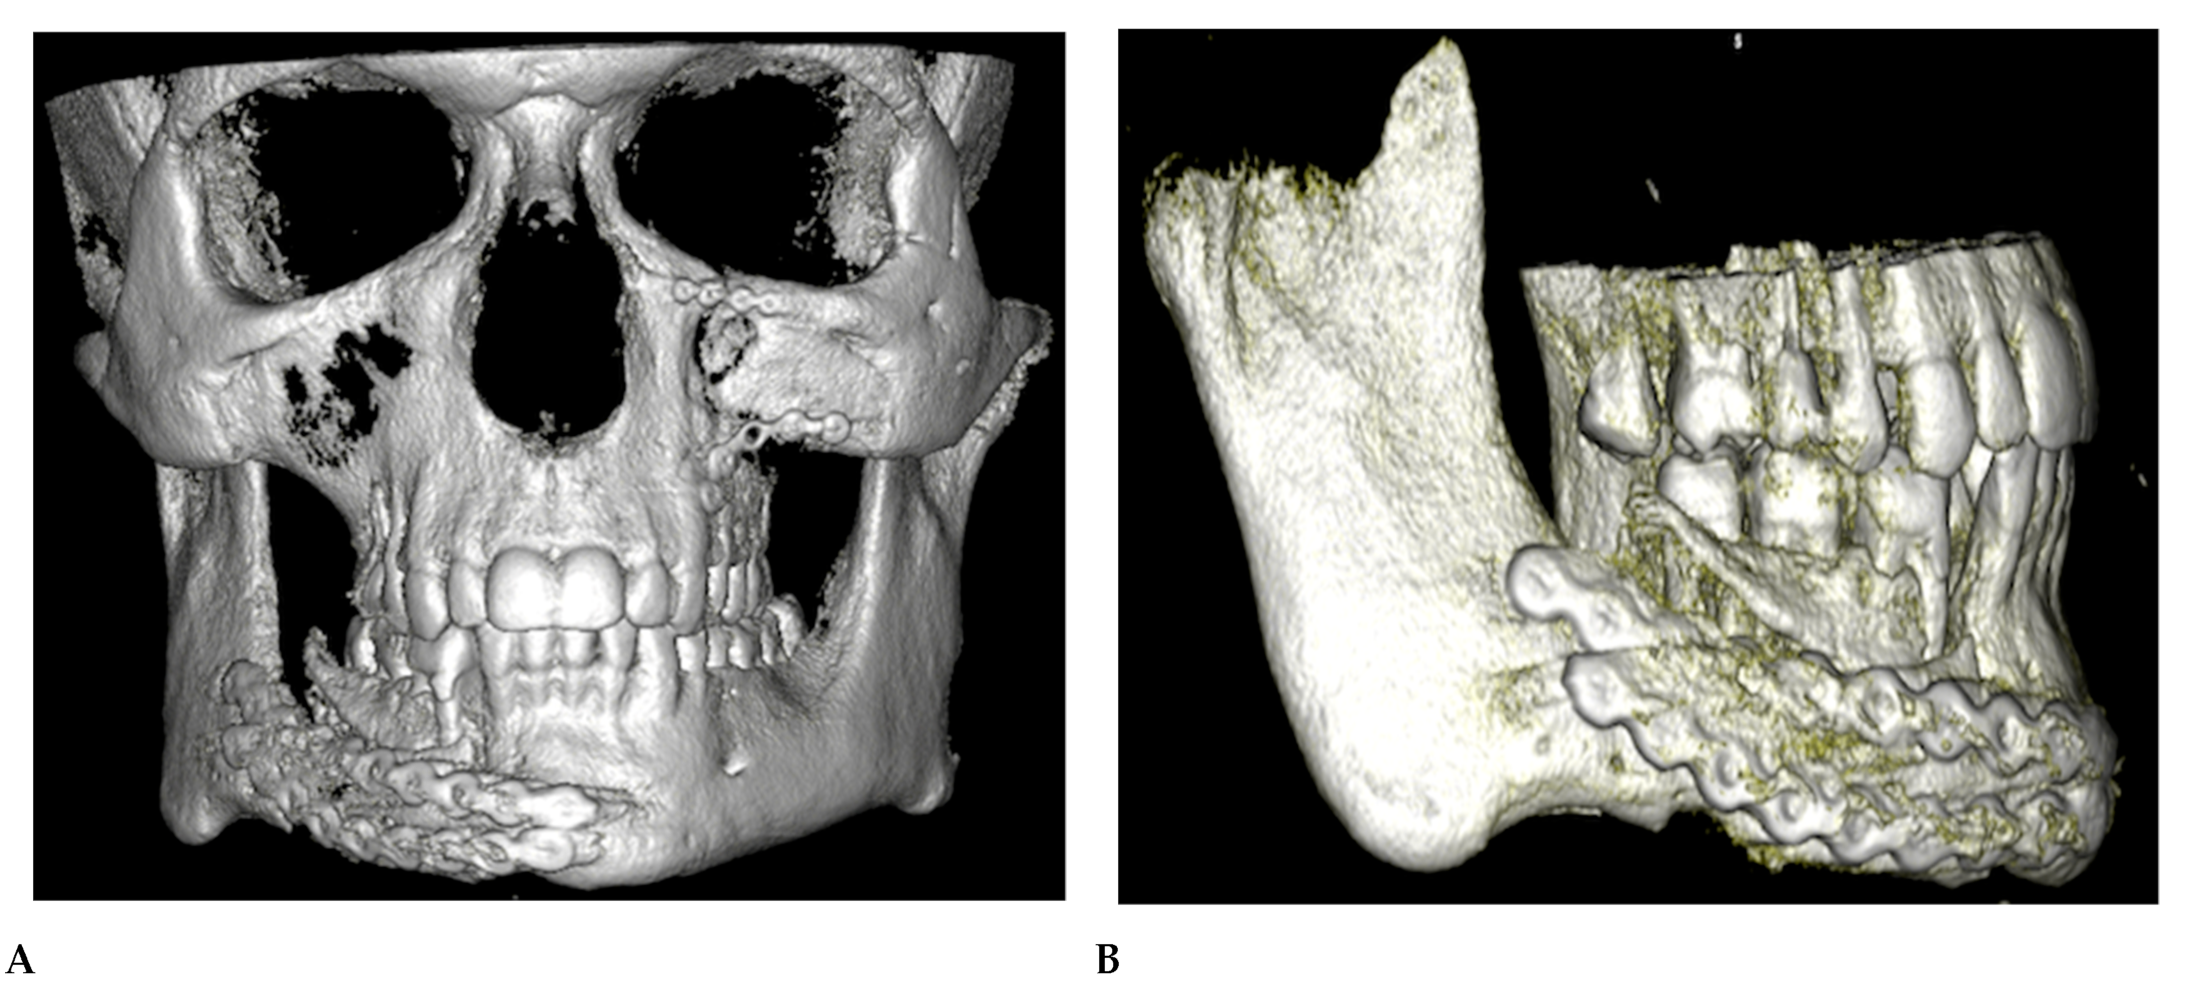

The patient presented to our department in March 2022, 6 months after the primary treatment, with gum loss and septic inflammation with a purulent exudate in the mandibular fixation region. The bone surface and the reconstruction plate were partially exposed. Partial necrosis of the alveolar bone was also observed. A control orthopantomogram (OPG) and a computed tomography (CT) scan of the viscerocranium presented centripetal roll rotation of the right mandibular segment, a lack of the bone formation at the osteosynthesis site, and insufficient stabilization of the fracture (Figure 1). Furthermore, we observed malocclusion and difficulties in proper masticatory function on the right side of the patient’s dentition due to their partial lack of teeth and improper inward tilting of the lower right molars.

Figure 1. (A) OPG X-ray(prior to the surgery). (B) 3D reconstruction of the maxilla and mandible prior to surgery.